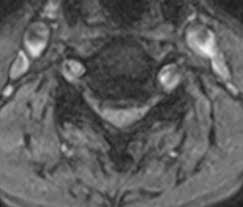

Boyun Fitigi